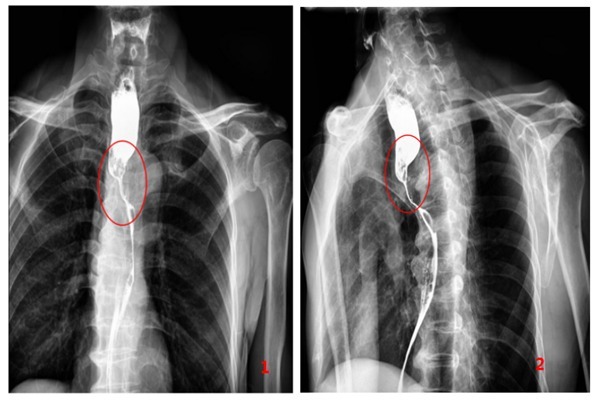

2、CT断层扫描/磁共振(MRI)。

它不仅能看到病灶的部位、长度,还能看到食管壁的厚度、肿瘤外侵、同邻近脏器的关系、颈部或纵隔淋巴结的转移情况以及肺部转移情况。